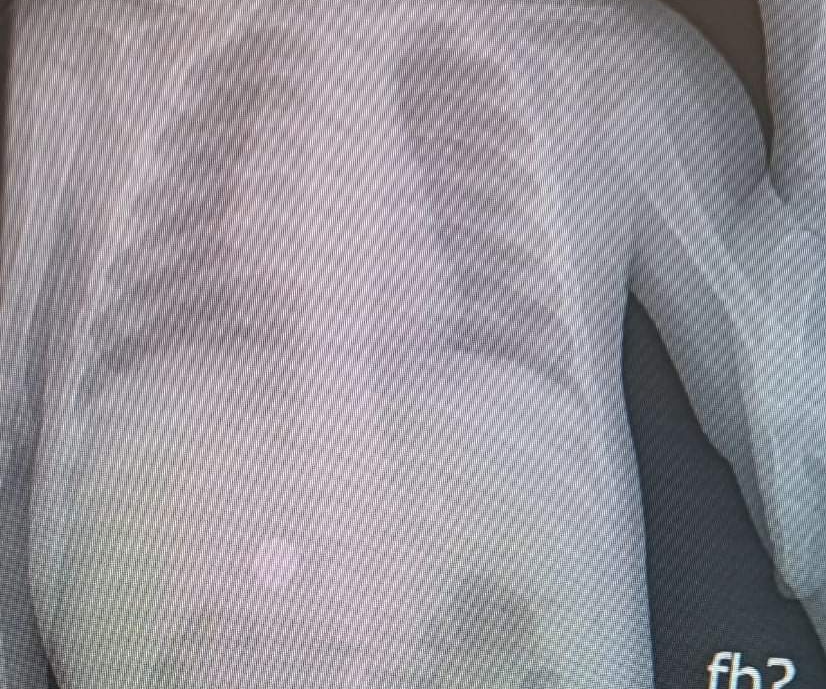

שוב מקרה של פעוטה בת 11 חודשים שבלעה סוללה. נראה שמדובר באחד הדברים האהובים על תינוקות. כפי שרואים בצילום הסוללה הגיעה לאזור הבטן.